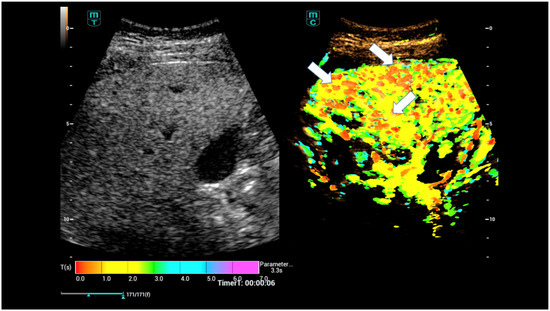

High-Resolution Contrast-Enhanced Ultrasound with SRCEUS for Assessing the Intrahepatic Microvasculature and Shunts in Patients with Hereditary Haemorrhagic Teleangiectasia (Osler’s Disease)

3. Results